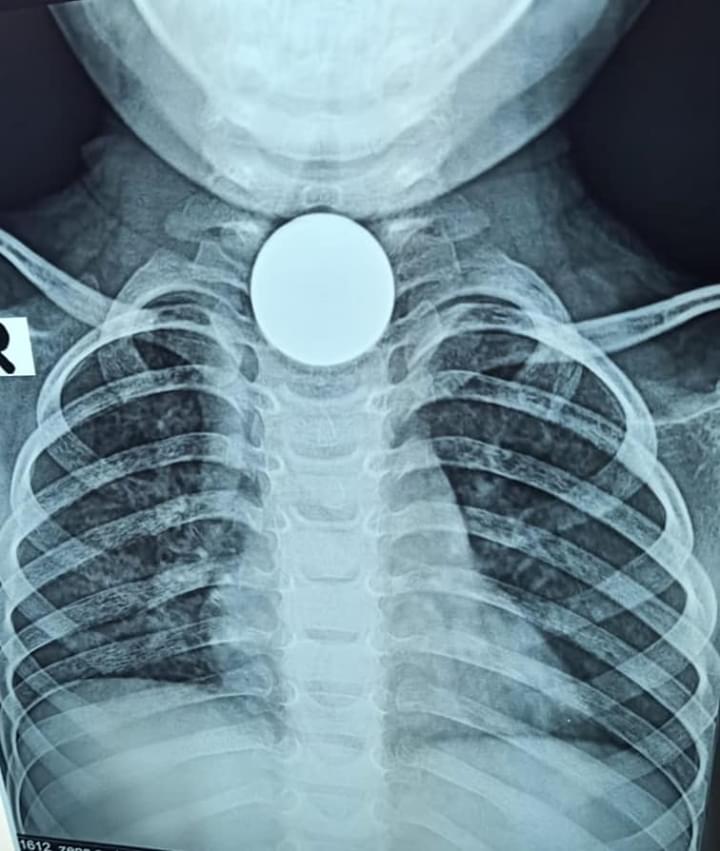

ترجع الواقعة أن الطفله بلعت نصف جنيه من دون أن يلاحظ أحد فى البيت، وبعدها بدأت تعانى من صعوبة في البلع ورفض للأكل ونوبات ترجيع متكرر كان يستجيب للعلاج بشكل جزئي ثم بدأت تعانى من صعوبة فى التنفس ونوبات اختناق وكانت تأخذ جلسات استنشاق، وبعد معاناة السبعين يوميا من تعب الطفله طلب الطبيب المعالج عمل أشعة على الصدر والتى أظهرت وجود جسم معدنى يشبه العملة المعدنية فى المرئ .

تم استقبال الحالة بمستشفى الاطفال وتم اجراء أشعة مقطعية التى أظهرت وجود العملة المعدنية فى المرئ.

وقام فريق العمل بوحده الجهاز الهضمي  بعمل منظار للمرئ وتبين وجود نصف جنيه بحاله صدأ كامل مما يدل على وجوده لفترة طويلة فى هذا المكان ووجود تقرح من حوله وتم استخراجه بالمنظار دون الحاجة للتدخل الجراحى وخرجت الطفلة من المستشفى بحالة جيدة .